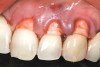

A 54-year-old non-smoking woman presented for correction of deep-wide gingival recession in the maxillary anterior (Figure 1 through Figure 3). The patient’s desires were to correct the gingival recession, balance the heights of contour of the tissues, and possibly undergo esthetic enhancement of the maxillary anterior with veneer restorations.

Figure 1  Case One Pretreatment clinical view, Case 1, maxillary right.

Figure 1